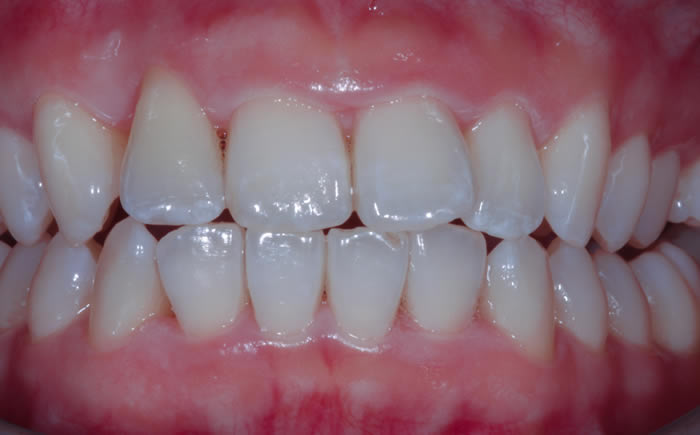

Dental implants used to replace two upper front teeth

Missing upper front tooth replaced by dental implant and crown